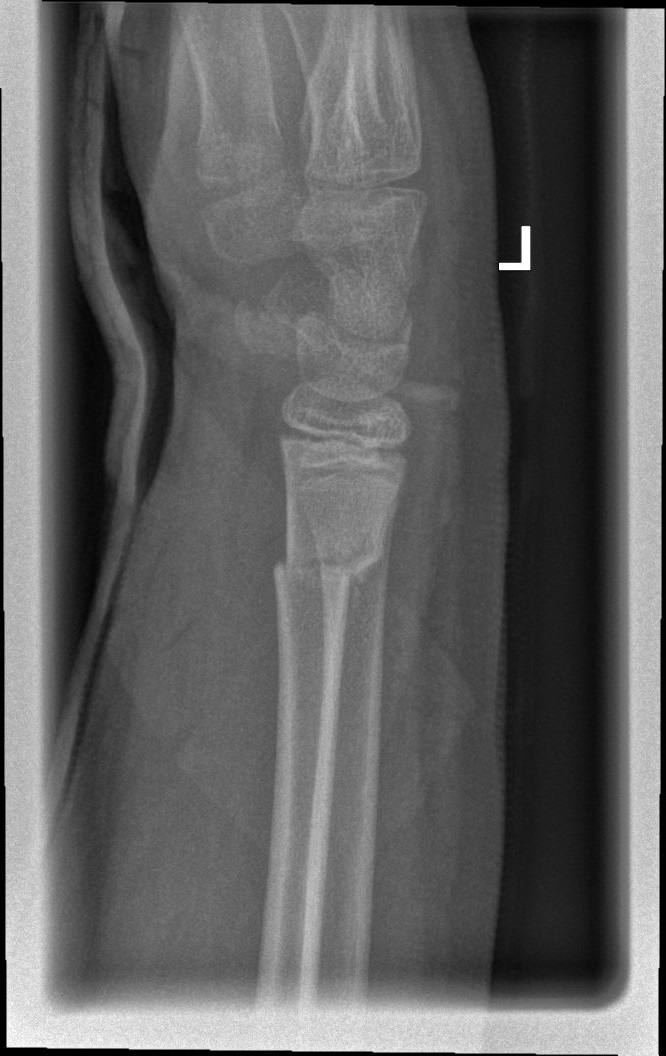

Fall 3

• Alter: 8 Jahre

• Geschlecht: weiblich

• Knochenbruch-Lokalisation: Arm (Ellenbogen / Supracondyläre Humerusfraktur Typ 4)

Tag 0

Tag 1

Jahr 7